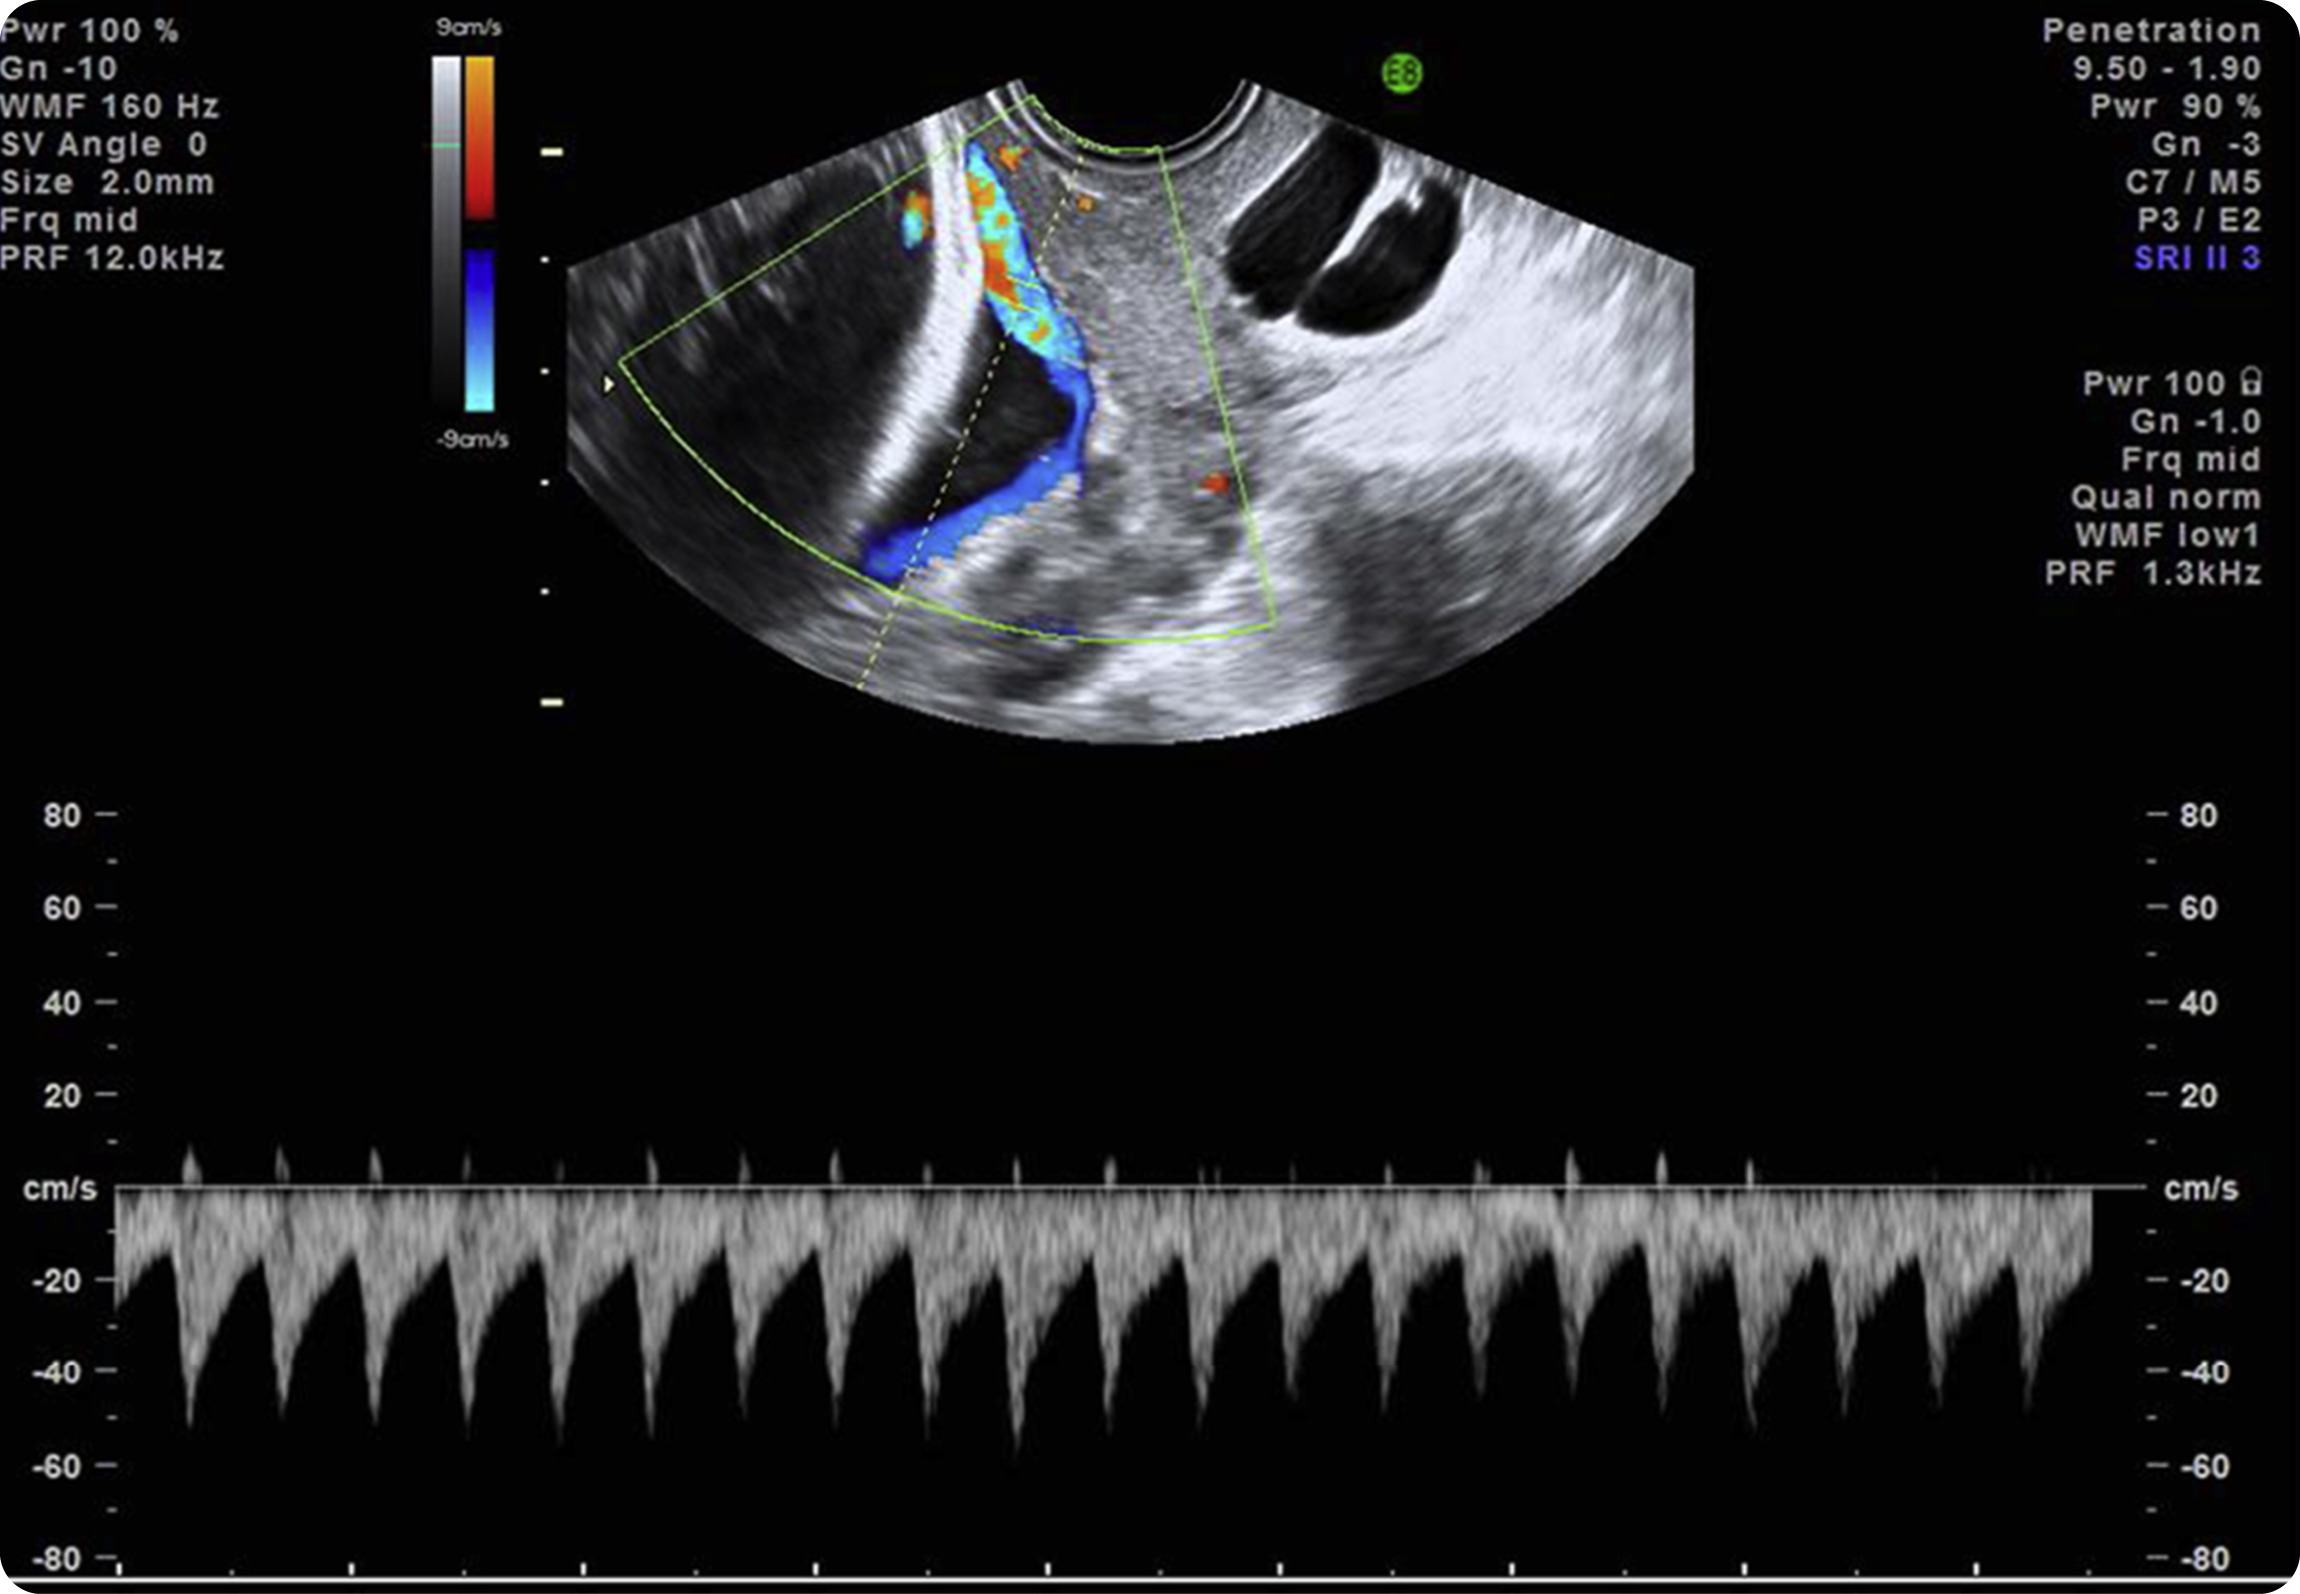

Figure 3. Transvaginal ultrasound scan with color Doppler image and pulsed wave Doppler image shows fetal heart rate

Image of vasa previa.

Pulsed wave Doppler of the vessel over the cervical os depicts a fetal heart rate, confirming a diagnosis of vasa previa.